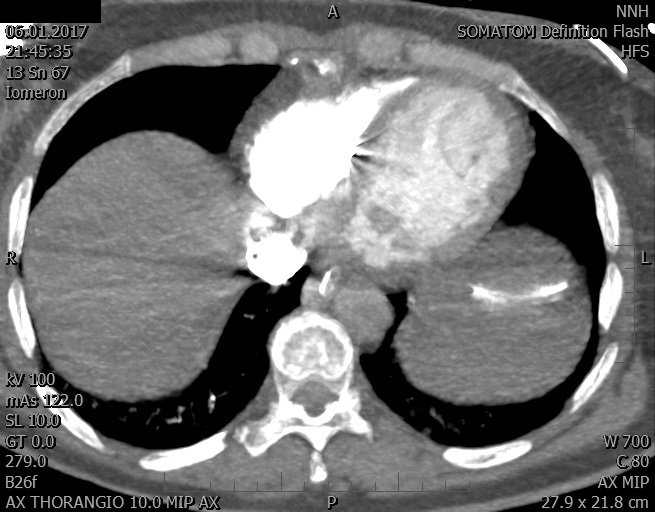

Video 1 - Akutní koronarografie prokázala normální nález na věnčitých tepnách s výjimkou suspekce na lehký spasmus na pravé koronární tepně.Echokardiograficky byla zjištěna těžká dysfunkce dilatované levé komory s nezvětšenou pravou komorou (video 2).

Video 2 - Echokardiograficky byla zjištěna těžká dysfunkce dilatační levé komory s nezvětšenou pravou komorou.Pro nejasnou příčinu zástavy jsme provedli i vyšetření výpočetní tomografií (CT), které vyloučilo plicní embolizaci (série 1 - soubory na konci článku). V den přijetí při přetrvávající oběhové nestabilitě byla nemocná opakovaně defibrilována pro fibrilaci komor se stabilizací rytmu po podání amiodaronu a mesocainu. Dle hemodynamických měření se jednalo o těžký kombinovaný šok. Vstupní laboratorní vyšetření bylo bez větších pozoruhodností. Posléze jsme doplnili anamnézu od příbuzných a zjistili, že pacientka užila do dvou hodin před srdeční zástavou první tabletu amoxicilinu na lehký respirační infekt. Při nevýtěžnosti vstupních vyšetření a nových anamnestických informacích jsme doplnili 14 hodin po kolapsu vyšetření koncentrace tryptázy v séru, která byla extrémně zvýšena (tabulka 2), což nás vedlo k podezření na anafylaxi.